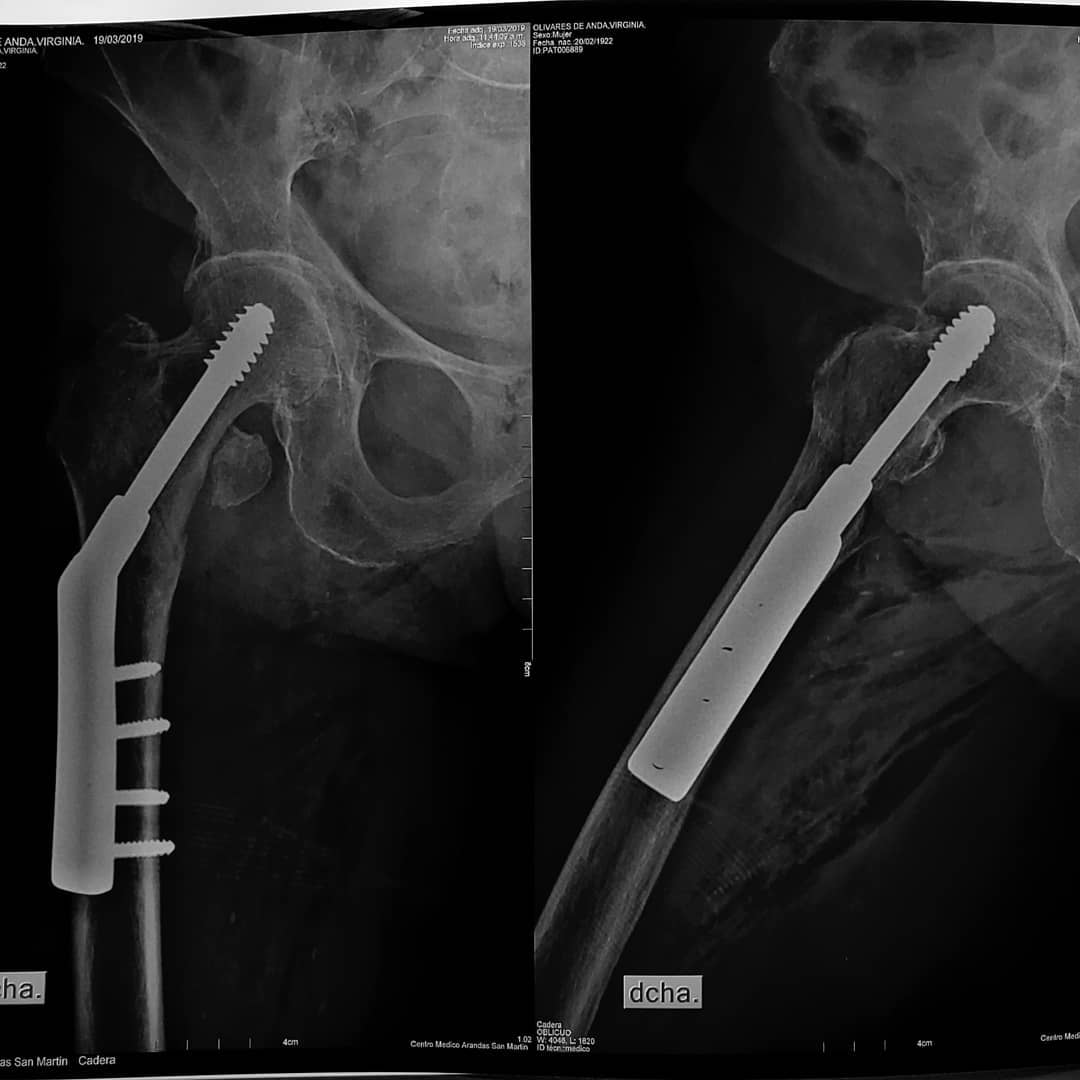

Los traumatismos de alta o baja energia, producen perdidas en la continuidad osea, que puede afectar la articulacion, todas requieren tratamiento, ya sea la inmovilizacion o la cirugia.

El tratamiento quirurgico consiste en placas, clavos y fijacion externa, inclusive protesis articulares.

Fracturas en adulto

- Atencion integral de paciente fracturado de hueso largo y/o corto, con tratamiento adecuado para su pronta recuperacion y reincorporacion de las actividades diarias.

- Cirugia de fractura articular, donde se busca minimisar las secuelas de fractura con una actividad con el menor dolor posible